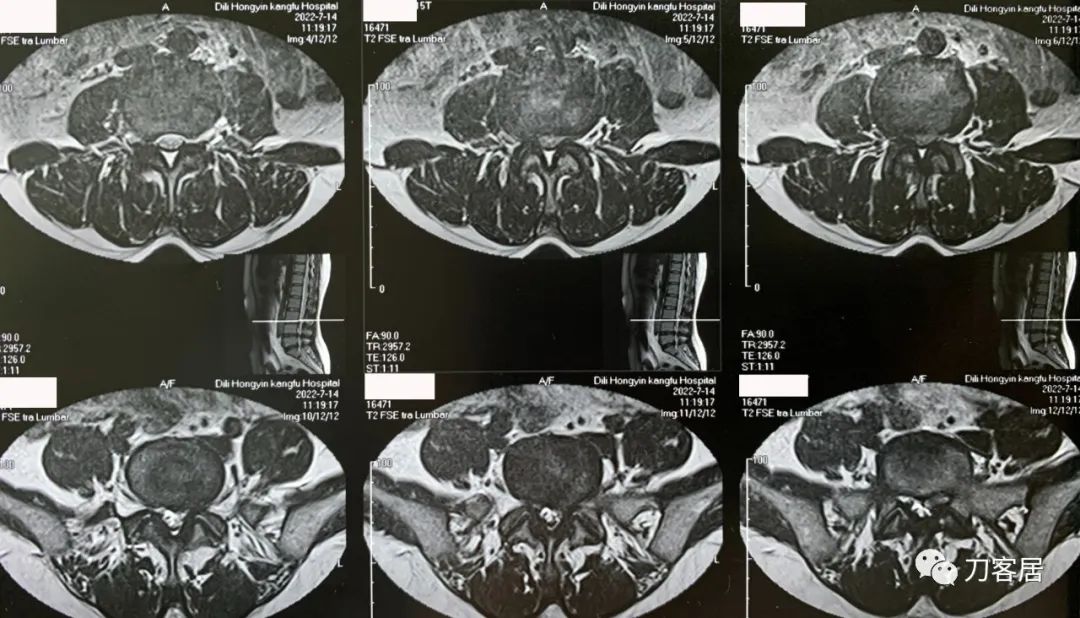

图3. 20220714外院腰椎MRI3,提示腰4-5椎间盘突出,椎管狭窄。

图4. 20220714外院腰椎MRI4,提示腰3-4椎管狭窄,腰5骶1椎间盘突出,左旁侧型。

不能坐,晨起严重,姿势变化时明显,站卧无影响,坐姿后左臀部并左小腿抽痛麻,行走无影响。腰椎MRI提示腰3-5椎间盘突出,腰4-5,腰5骶1为重,腰5骶1左侧突出明显,并腰椎管狭窄。腰椎及骨盆X线片未见异常。骨密度提示骨量正常,且有所增高。昨日(8月4日)可连续行走1.6km。